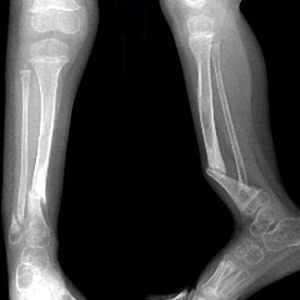

Диагностировать ложный сустав можно рентгенологическими методами. Рентгенограмма покажет два варианта псевдоартроза:

- Гипертрофический – это избыточное разрастание тканей кости в месте перелома при условии нормального кровоснабжения. Данная патология характеризуется быстрым ростом костной ткани в области перелома. Рентген покажет сильное увеличение расстояния между концами отломков.

- Атрофический – формирование псевдоартроза при недостаточном или отсутствующем кровоснабжении. На рентгенограмме заметны четкие границы краев отломков, которые удерживает соединительная ткань, хотя она не достаточно прочная, чтобы полностью обездвижить участок образования псевдоартроза.